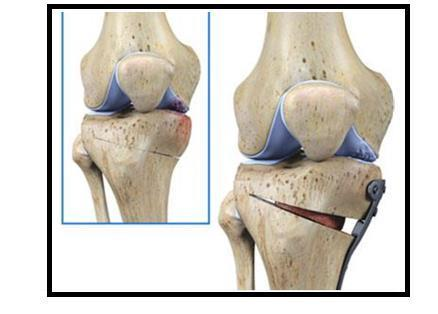

据了解,保膝治疗的两种主要手术方式是截骨术和单髁置换术,可以精准解决患者膝关节疼痛的病因,处理膝关节病变,最大限度保留患者膝关节原有功能。其中,截骨术是通过纠正下肢异常力线,改变膝关节异常应力集中,在解决患者疼痛症状的同时,进一步阻止异常应力对膝关节的进一步损伤,膝关节内部所有的软骨韧带半月板都得到了保留,患者恢复健康后,拥有完全正常的膝关节功能。内侧单髁置换术,精准置换患者膝关节内侧间室磨损,而膝关节外侧健康的软骨和半月板得到了保留,膝关节的内外侧副韧带、前后交叉韧带都维持原有的状态,为患者保留原有的膝关节运动功能。

图片

膝关节单髁手术示意图